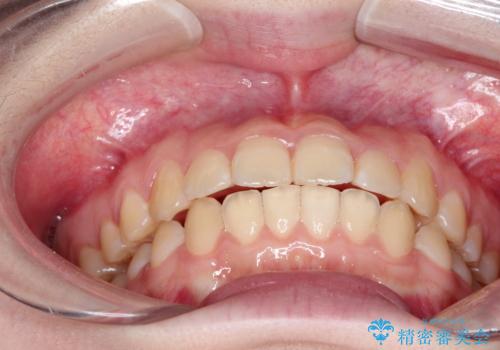

- 1年2ヶ月

- 10-30回

ワイヤー矯正が1か月に1回程度来院が必要なのと比較すると、2-3か月に1回の来院でもよいので(症例によります)、通院回数を減らすことができて、患者様の負担を減らすことができます。